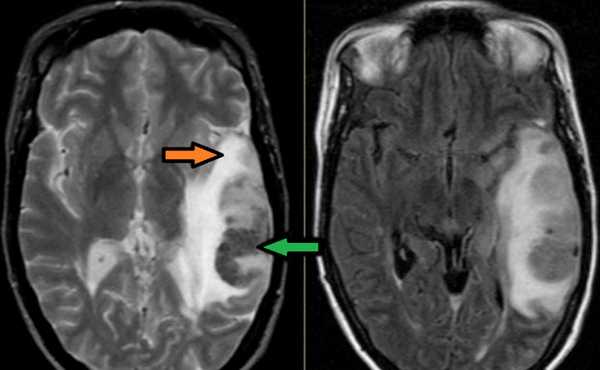

Как указывалось выше, в случаях возникновения клинической картины церебрального венозного тромбоза по ходу вен и синусов на МРТ головного мозга в части случаев обнаруживается зона ишемии и геморрагии.

МРТ головного мозга: отмечается сочетание вазогенного (оранжевая стрелка), цитотоксического отека и кровоизлияния (зеленая стрелка). Данная МР-картина, а также расположение патологической зоны в проекции височной доли, заставляет задуматься о геморрагическом венозном НМК вследствие тромбоза вены Лаббе. Для подтверждения необходимо проведение МР-венографии или МРТ с контрастным усилением.